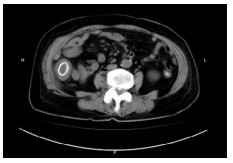

1 资料与方法病例1,患者女,72岁,2020年9月2日因“腹痛3 d”来本院急诊,拟“升结肠肿瘤伴肠梗阻”收住院。半月前因“胆囊结石”在当地医院行腹腔镜下胆囊切除术。本次入院查体:腹部膨隆,右下腹部压痛明显,轻度反跳痛。WBC13.3×109/L, N 84.0%。腹部增强CT提示升结肠管壁不规则增厚伴管腔狭窄,回盲部及远端回肠扩张明显(图 1)。肠镜检查:升结肠肿物,予取病理活检后,在肠道狭窄处行肠梗阻金属支架植入解除梗阻(以维持肠腔的通畅性和减少肠道毒素的进一步吸收)。肠镜病理提示:(升结肠)管状绒毛状腺瘤,部分高级别上皮内瘤变。3 d后复查腹部平扫CT示回盲部及远端回肠原先扩张的肠腔已明显缩小(图 2)。因患者既往有糖尿病史,时常合并胸闷胸痛,心电图示侧壁T波直立,心内科会诊建议行心脏冠脉造影。冠脉造影提示心脏左前降支中段狭窄约百分之八十,远端约百分之九十狭窄。经多学科讨论后认为患者目前急性肠梗阻症状已经缓解,建议可先予冠状动脉药物涂层支架植入术,再予以替格瑞洛口服抗凝治疗,1个月后再次入院行结肠肿瘤手术。患者于2020年10月9日再次入院行腹腔镜下右半结肠癌根治手术,手术过程顺利。术后病理报告:(升结肠)高-中分化腺癌,T3N1M0。患者术后13 d出院,并接受了后续的规律化疗。目前患者恢复良好。

| 图 2 放置升结肠支架3 d后复查腹部平扫CT示回盲部及远端回肠原先扩张的肠腔已明显缩小 |